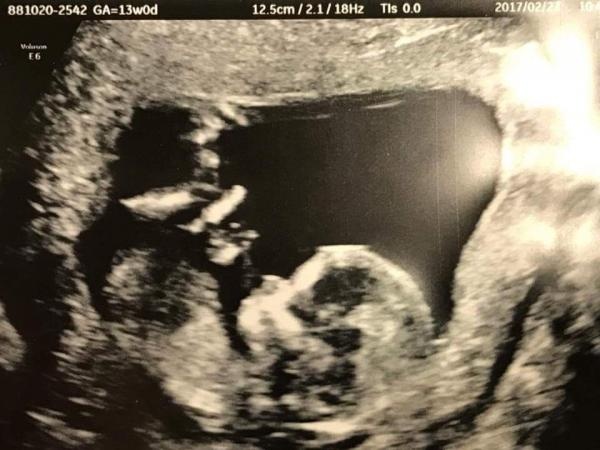

Linalouice Äldre 28 Feb 10:08 629 svar Återställ Anmäl Du ogillar detta Jag gissar kön från era tidiga ultraljud! V 13+5. Någon gissning på könet?